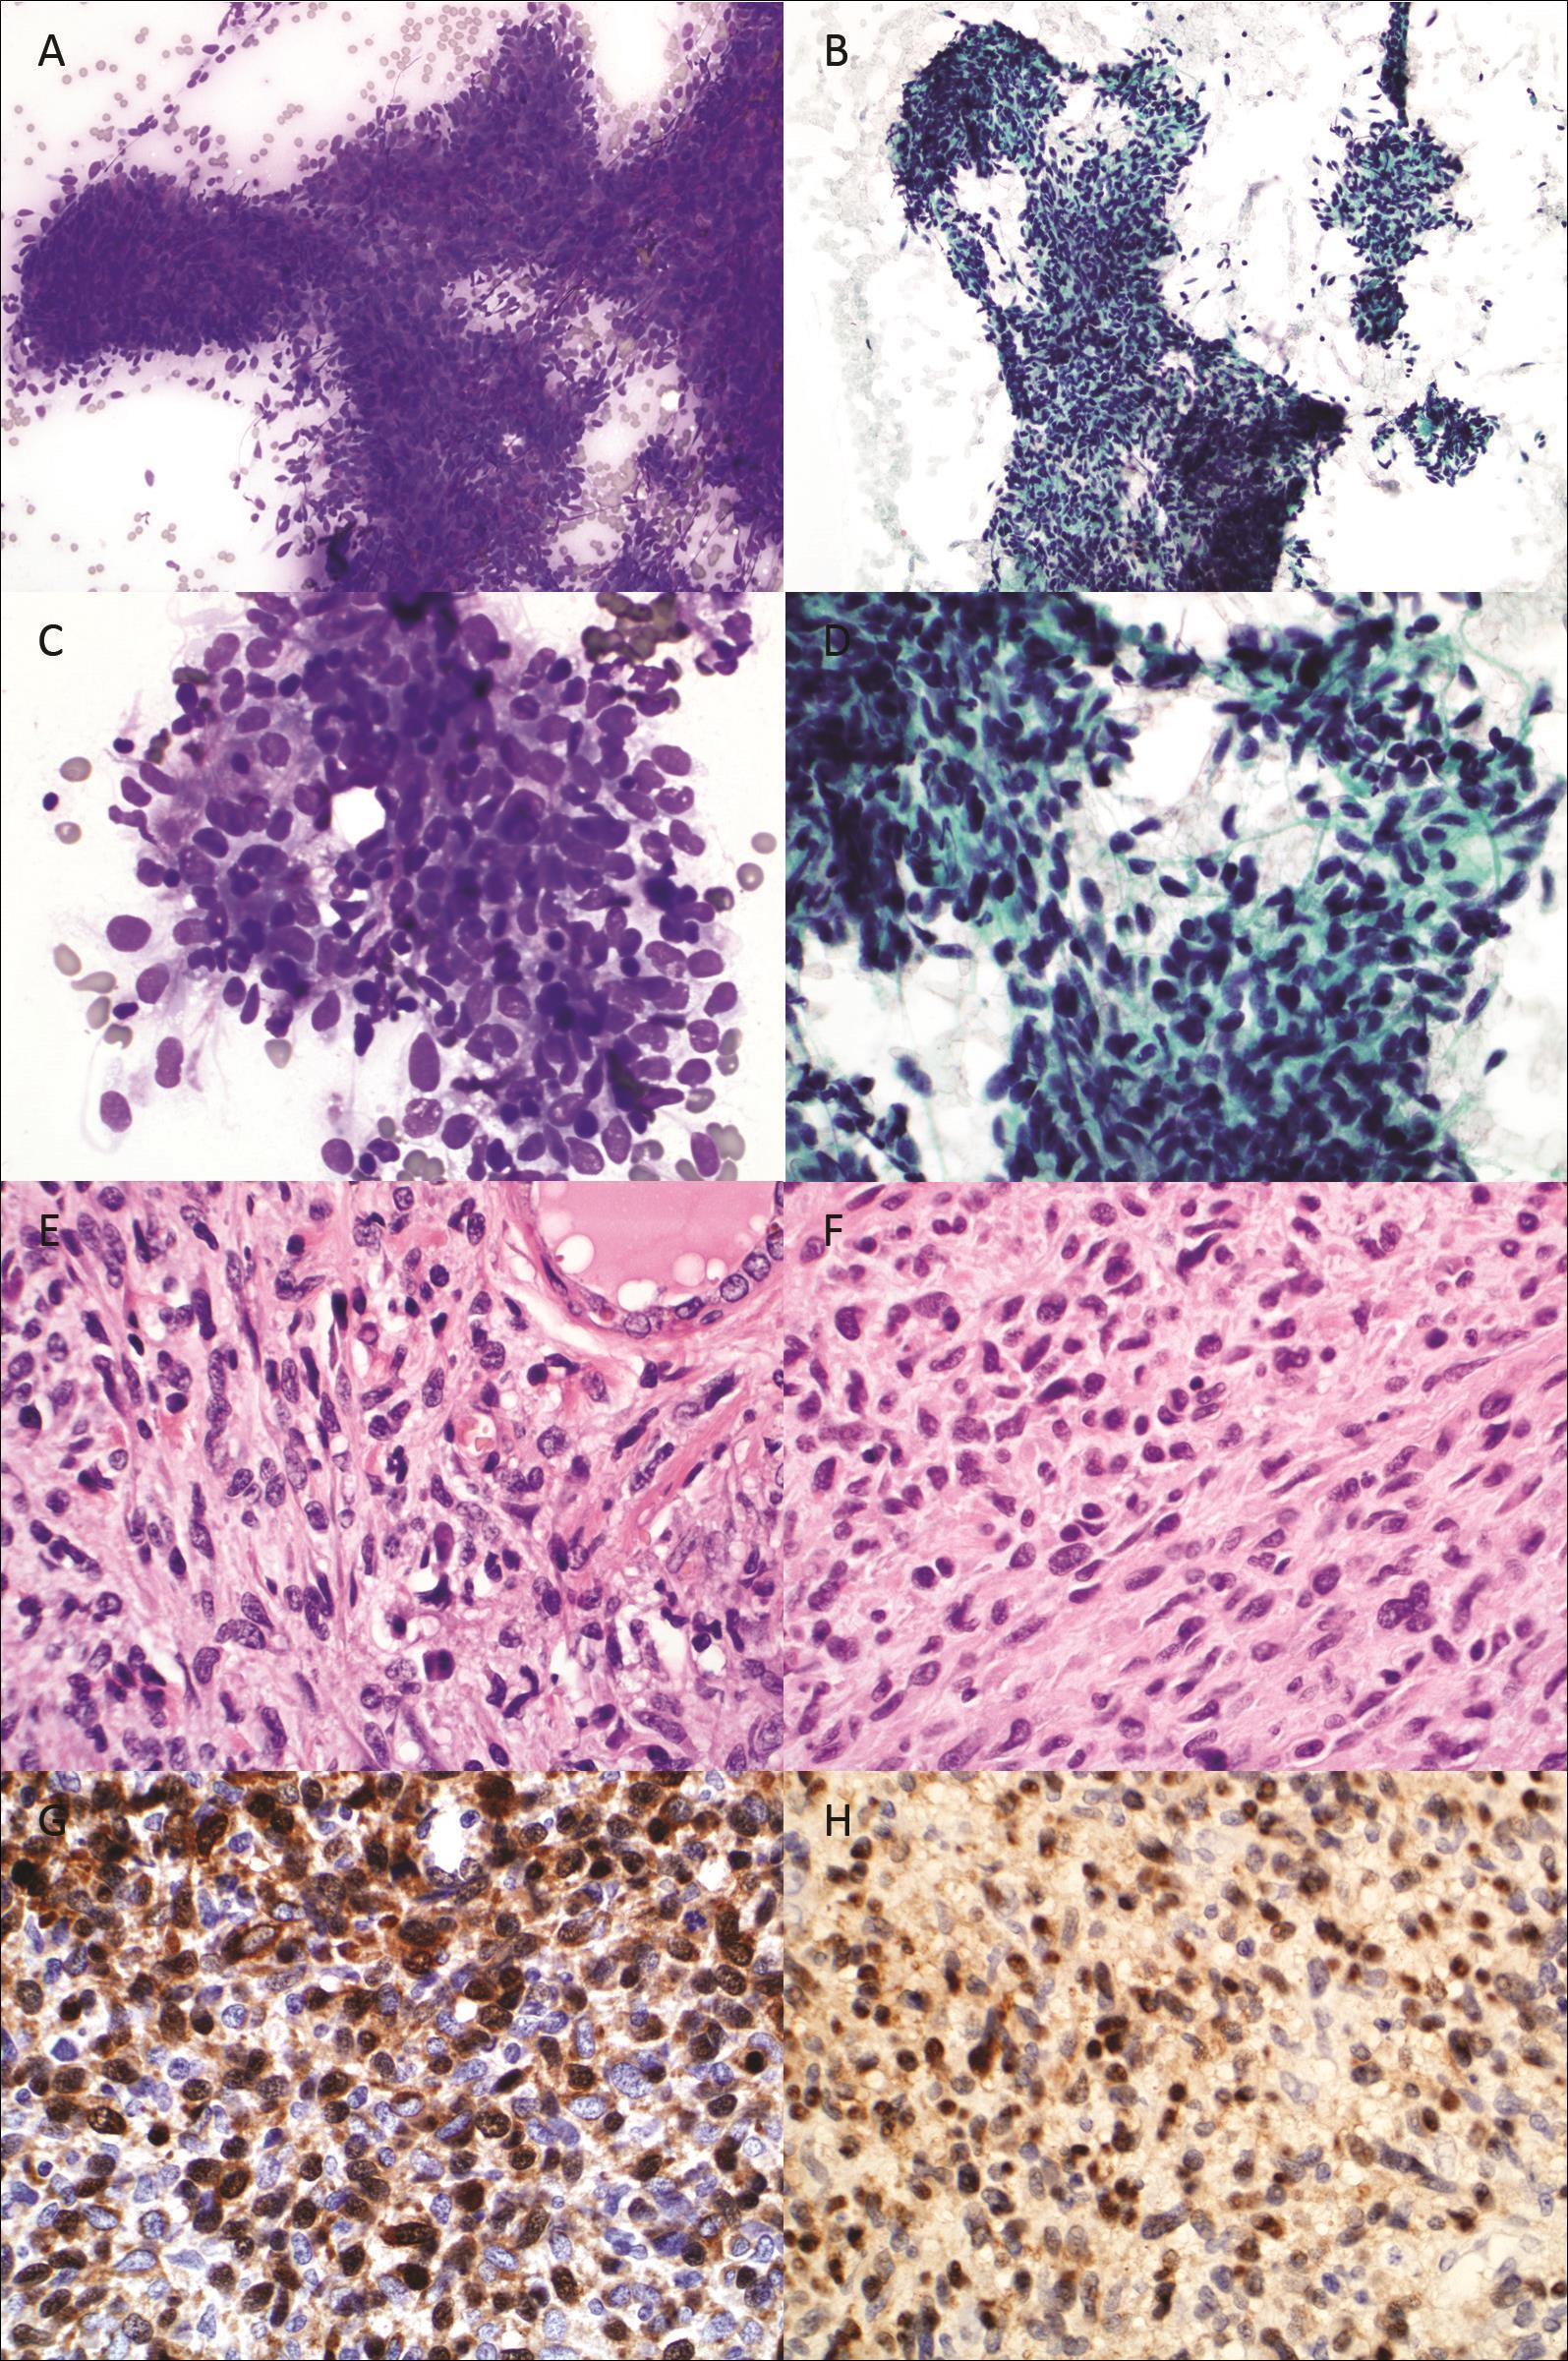

An ultrasound guided fine needle aspiration (FNA) was performed using 25 gauge needles on the right thyroid nodule.The air-dried FNA slides were stained with Diff-Quik stain and ethanol fixed slides were stained with Papanicolaou stain. Microscopic examination showed numerous loosely cohesive pleomorphic small spindle cells, some of which were arranged in short fascicles or haphazard pattern (Figure 1A to 1D).

Figure 1A and 1B.FNA cytology, Diff-Quik and Papanicolaou stain, respectively, x200. Fig. 1C and 1D: FNA cytology, Diff-Quik and Papanicolaou stain, respectively, x600. Fig. 1E and 1F: Histology from thyroid and small intestine, hematoxylin and eosin, x600. Fig. 1G and 1H: Immunostain for S100 on thyroid and small intestine, x600.

The nuclei were oval or spindle in shape, with hyperchromatic granular chromatin and inconspicuous nucleoli, and smooth nuclear membrane contours. The cytoplasm was scant to moderate in amount, and delicate. Some cells had long thin cytoplasmic projections. Normal thyroid follicular cells and colloid were present in the background. The cytomorphology of the current specimen was similar to that seen in the tumor of previous small intestine resection, while was different

from that seen in the previously resected melanoma. Based on the cytomorphology, a diagnosis of “consistent with metastatic MPNST from small intestine” was rendered.

Subsequently he underwent a total thyroidectomy. The thyroidectomy specimen demonstrated a white-pink lobulated mass measuring, 1.7 x 1.2 x 1.2 cm and several smaller nodules. The tissue containing tumor was formalin fixed, paraffin embedded, sectioned, and stained with hematoxylin and eosin (H&E) stain. The tumor was composed of sheets of pleomorphic spindle cells with cytomorphologic features similar to those seen in the FNA cytology. The tumor cells were arranged in fascicle or haphazard patterns. A high mitotic rate of 10 per 10 high power fields was noted (Figure 1E). The histology of the thyroid nodule was similar to that seen in the prior sarcoma of resected from the small intestine Figure 1F). Both the tumors were focally positive for S100 (Figure 1G and 1H). The thyroid tumor was negative HMB-45 and melan A. The histologic features and immunoprofile confirmed the cytologic diagnosis.